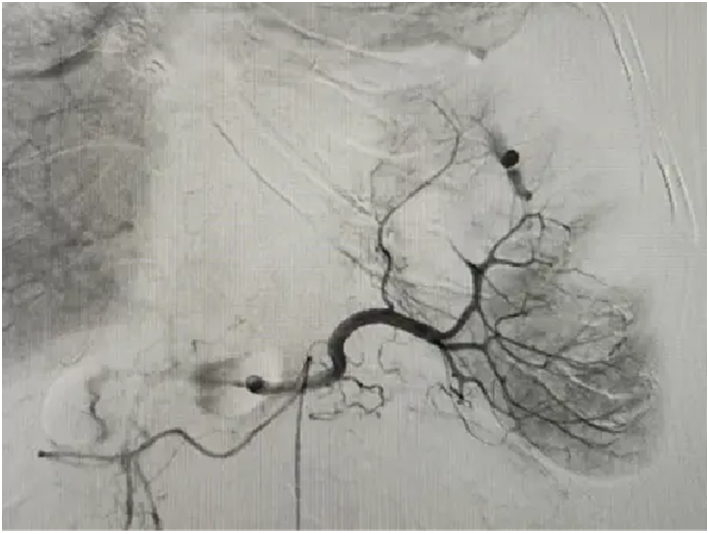

病例三:胸廓出血,精准“点穴”

陈先生(化名),因不明原因导致胸廓区域活动性出血。介入团队迅速行动,通过急诊血管造影快速锁定责任血管,实施超选择性栓塞治疗。微创穿刺,精准“点穴”,患者转危为安。